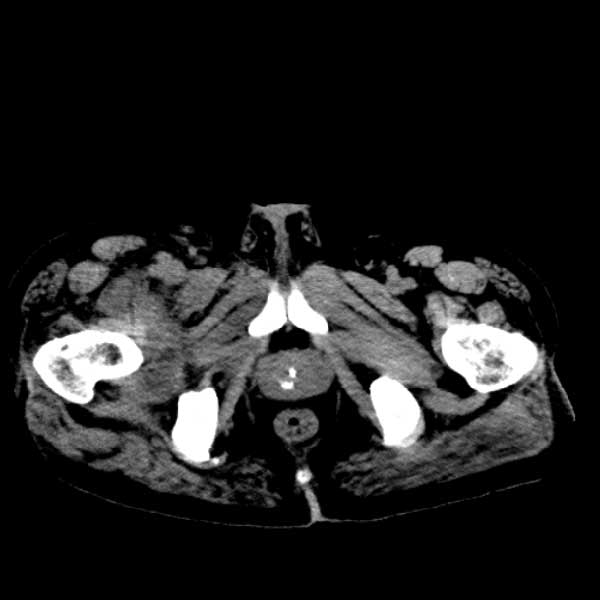

标题: CT13513:男 71 腹部疼痛20余天,近几天高热就诊,骨窗未见异 [打印本页]

标题: CT13513:男 71 腹部疼痛20余天,近几天高热就诊,骨窗未见异

考虑感染性病变可能性大,起源于阑尾?

感染,脓肿形成

考虑为化脓性阑尾炎.脓肿形成.及多肌肉累及.

考虑右侧腰大肌脓肿,向右髂窝、右腹股沟流注。

支持化脓性阑尾炎伴右髂窝脓肿、腰大肌腰方肌脓肿形成。

考虑腹腔及盆腔化脓性炎症,累及右侧髋关节及腹股沟区.

首先考虑化脓性阑尾炎伴腰大肌、腰方肌脓肿,不除外回盲部结核。

回盲部癌待排除。

患者肠镜检查考虑结肠癌,病理证实

患者肠镜检查考虑结肠癌,病理证实。肺部ct可见多发结节,考虑转移